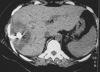

We report a new case of a brucellar liver abscess (brucelloma) in a young woman without previous remote brucellosis who presented with pronounced systemic and mild local symptoms. Brucelloma is the result of calcification of a granoulomatous reaction induced by persistent Brucella in macrophages. It represents a rare manifestation that follows previously undetected brucellosis. We describe the findings in plain radiograph, ultrasound, computed tomography, and magnetic resonance images. Together with the positive serology, imaging yielded important elements supporting the diagnosis. Modern radiological techniques also contributed to the final therapeutic management, preventing unnecessary laparotomy. Sequencing confirmed the definite diagnosis of Brucella melitensis as the causative factor.